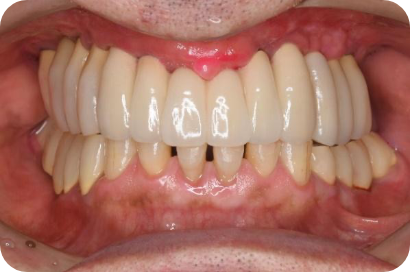

2025/12/10 / 最終更新日 : 2025/12/10 tom インプラント インプラント治療 – 複数本で安定した噛み心地を実現 インプラントを用いた治療例 複数のインプラントを使用し、固定式でしっかり咬めるようにする。 治療前後の比較 Before After 治療内容 インプラント治療 施術費用 通院回数 通院期間 メリット リスクと副作用